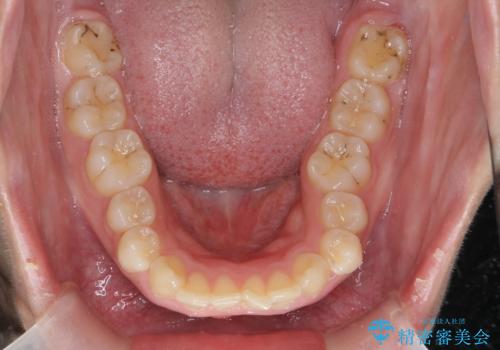

深い噛み合わせ、すきっ歯の改善 ワイヤーを用いたマルチブラケット矯正

- 噛み合わせが深く、前歯が突き出て隙間が出てきたことの改善を希望され矯正治療の相談で当院に初診来院されました。

ワイヤーを用いたマルチブラケット矯正を行うことで深い噛み合わせを改善し、前歯の隙間もなくし審美的な歯列へと治療をおこなっていきます。